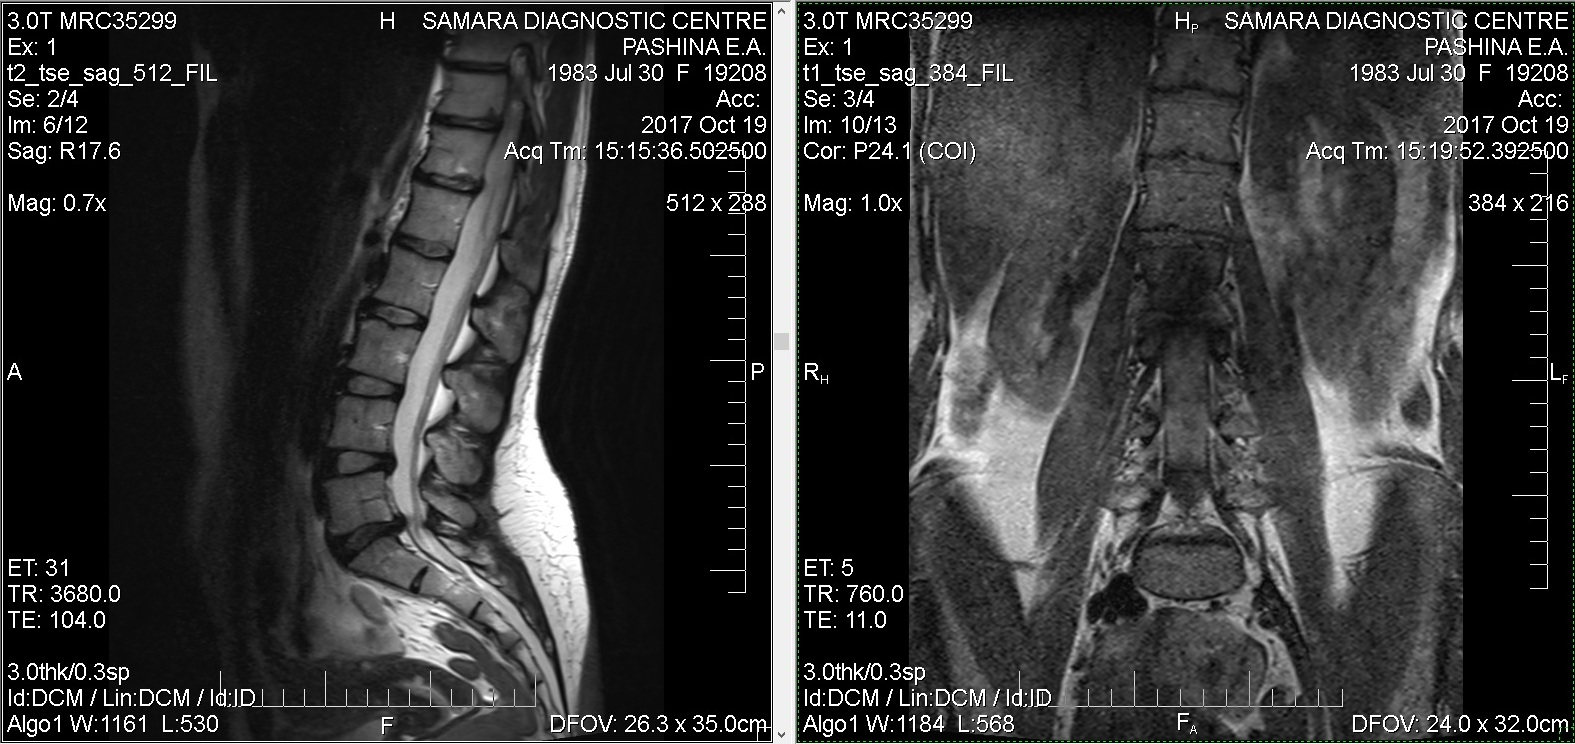

Тренировки с межпозвоночной грыжей.